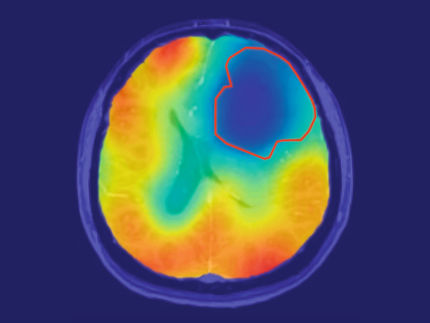

Detecting cancer cells before they spread - this is what the start-up QuantView from Kiel is working on. The spin-off from Kiel University (CAU) has developed a method with which magnetic resonance imaging (MRI) can be used much more sensitively. Using a new type of contrast agent and a signal amplification process, the team can make tumor remnants visible that conventional MRI has not been able to detect so far.

Healthy cells and cancer cells process sugar differently. Tumor cells prefer to convert pyruvate into lactic acid, thereby generating a clear metabolic signal. After the injection, areas with high lactic acid production glow brighter in the MRI and thus reveal active cancer cells.

The contrast agent used by QuantView contains hyperpolarized pyruvate. Using the physical method PHIP+ (Parahydrogen Induced Polarization), the team brings almost all atomic nuclei of the sample into the same magnetic alignment and amplifies the MRI signal by a factor of 24,000. This enables the system to detect even the slightest metabolic changes in the tumor.